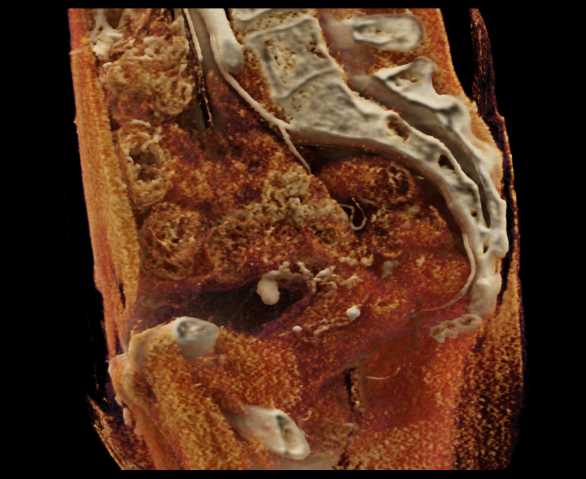

Urachal Carcinoma of the Bladder